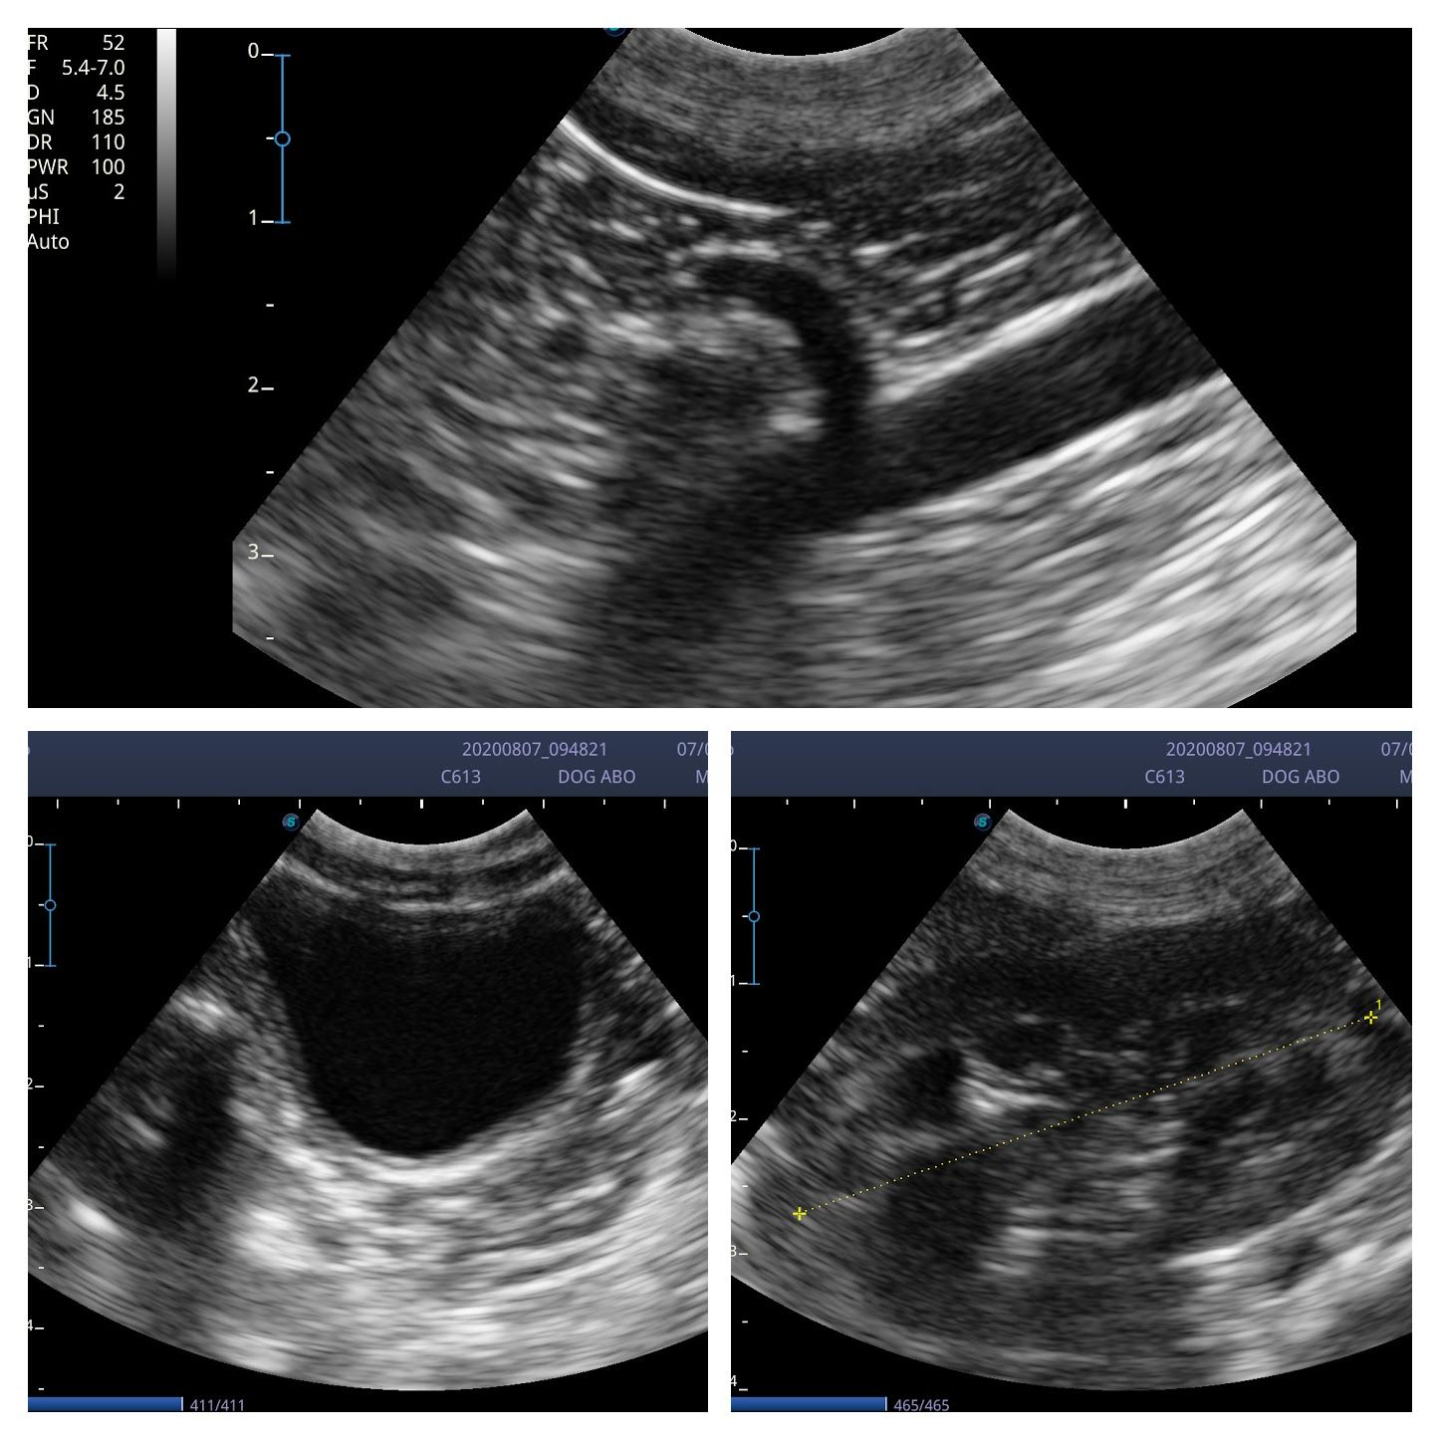

I scanned with the microconvex C613 probe (4-13MHz) and the linear L741 (4-16MHz). Although the linear probe gives great images, the 4.5cm footprint does make maneuverability around a small cat abdomen a little tricky. The microconvex probe was used in a few dogs up to 20Kg and managed to view the liver perfectly well.